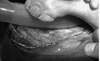

Figure 29-3. Identification of the individual pulp chambers of mature equine cheek teeth using a recently modified system of pulp nomenclature by du Toit et al.4 The 06s (left side of figure) have six pulp horns. The 07s to 10s (center of figure) have five pulp horns. The 11s (right side of figure) have six or seven horns.

Figure 29-5. Cross section of a maxillary cheek tooth (Triadan 07-10 position) showing the five numbered pulp horns (P1 to P5), rostral infundibulum (RI), and caudal infundibulum (CI). As is often the case, the rostral infundibulum is incompletely filled with cementum and may later develop caries.